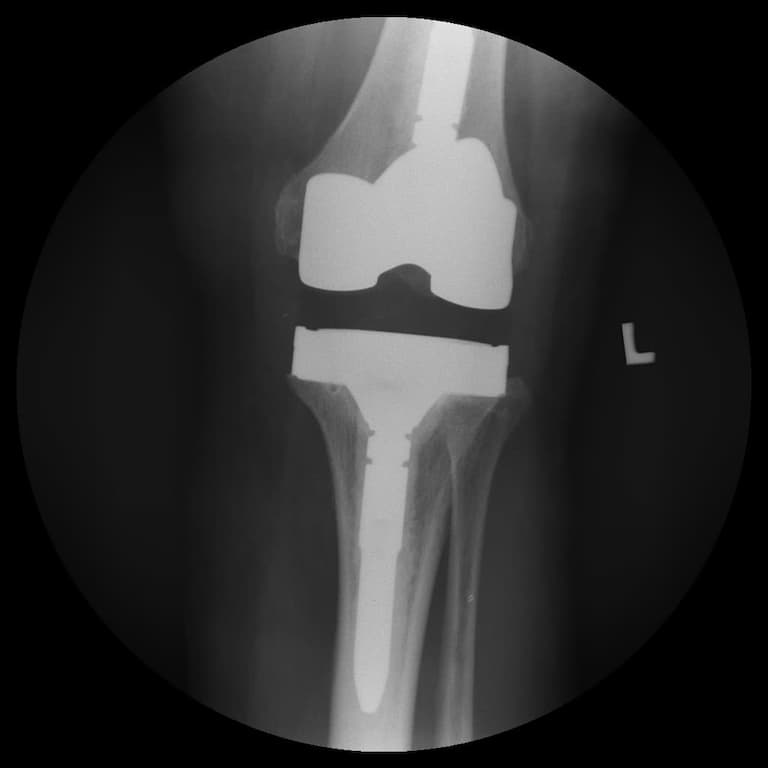

Үе дайрсан ясны анхдагч хавдар, ясны дутмагшлын үед хийгдэх мэс засалimg15Үе дайрсан ясны анхдагч хавдар, ясны дутмагшлын үед хийгдэх мэс засалimg16

Зураг 3. Мэс заслын дараах рентген зураг. Эгц урд, хажуугаас авсан байдал